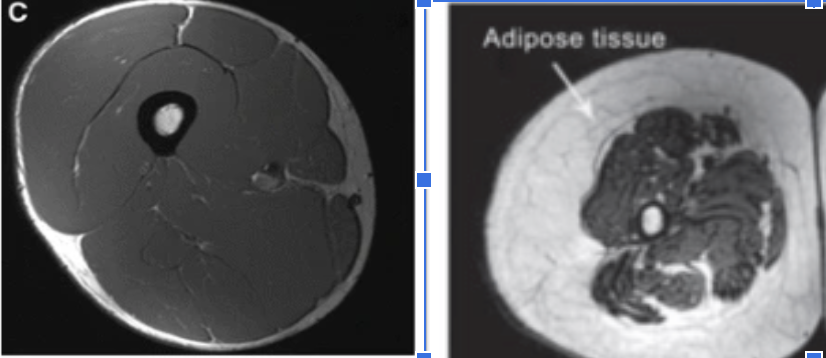

This is a cross-section of a thigh.

On the left is a 24 year old healthy male

-dense femur bone at the center

-thick muscle tissue

-some subcutaneous fat

Compare that with a 74 year old sedentary man on the right with atrophied muscles, thin bone and high fat deposits. x.com

On the left is a 24 year old healthy male

-dense femur bone at the center

-thick muscle tissue

-some subcutaneous fat

Compare that with a 74 year old sedentary man on the right with atrophied muscles, thin bone and high fat deposits. x.com